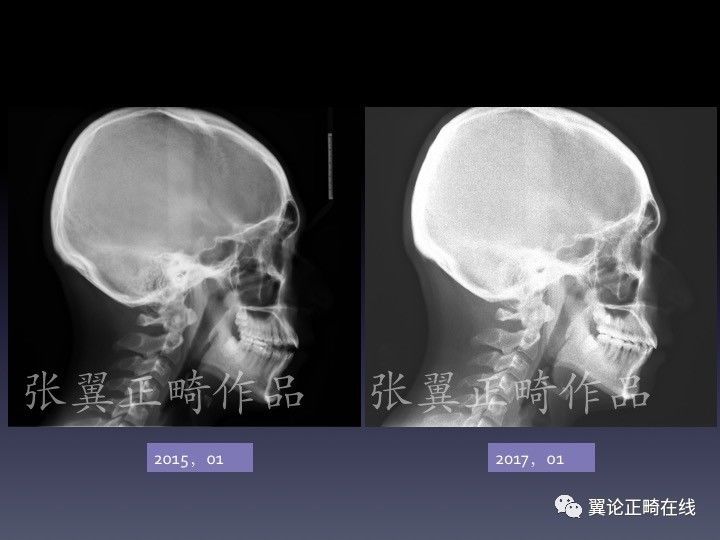

病例展示